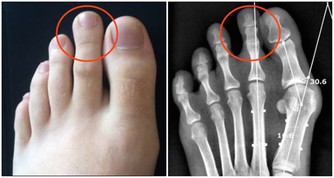

人之所以疼痛部位、 患的疾病不同,就是因為不同的地方被瘀血堵塞。瘀血還和哮喘、牛皮癬、抑鬱類疾病、婦科疾病的關聯很大;水濕和脾胃腎臟的功能、肌肉類疾病、黃斑病等關聯很大;食瘀和心血管疾病、膽囊胰臟疾病、瘡疔癰膿類疾病的關聯很大。